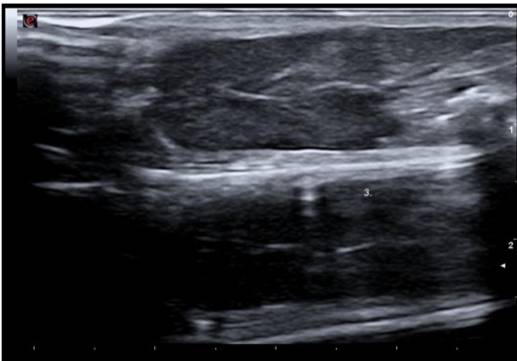

Ultrasonographic findings

Ultrasound imaging was obtained from 38 mice, of which 19 (50%) had a homogeneous and normoechoic liver parenchyma and no tumors on gross pathological examination and histologic sections (Fig. 3). In the remaining 19 mice (50%), at least one nodule measuring between 1.2 mm and 17.1 mm in diameter along its longitudinal axis was detected by ultrasound. Liver nodule appeared as:

The ability of ultrasound to identify true negatives among truly healthy mice was 100%. Of the 27 mice negative for colorectal cancer on gross pathological examination, 19 were identified as negative because no liver tumors were detected in ultrasound images, and eight mice with non-nodular, hypoechoic images measuring <3 mm with homogeneous echotexture and indistinguishable borders at the site of implantation were identified as negative for cancer by ultrasound imaging.

The number of mice implanted with tumor fragments ranged from 3‒10 per patient, with the viability of tumor cells affecting xenograft success. Tumor implants were generated based on the gross features of the sample by removing areas of friable tissue with a scalpel. However, tumor cells were not microscopically assessed for freezing damage immediately after surgical resection, which could have reduced the number of xenograft failures and increase tumor growth rates. This variation in tumor growth rates can be explained by tumor heterogeneity. In the context of tumor biology, metastatic tissue can exhibit varying degrees of cellularity, necrosis, and fibrosis according to histological type and molecular profile. In the current study, all mice housed in the same microisolator cage were killed and analyzed when the presence of a tumor was verified by ultrasound imaging in at least one animal. This was similar to the procedure adopted in 2005, who also killed the mice once suspected metastases were detected by ultrasound, to minimize false negatives and improve the accuracy of ultrasound (Graham et al., 2005). Gross pathology revealed the presence of liver tumors in 11 mice, later confirmed in histologic sections. In eight mice, ultrasound findings measuring <3 mm in their largest dimension (cranio-caudal axis of the mouse) were identified by ultrasound as scar tissue at the site of implantation. Because no areas of scar tissue exceeded 3 mm in diameter on serial ultrasound imaging, a cut-off value of 3 mm for scar tissue can be tested in larger series. Liver tumors detected by ultrasound were serially followed to track tumor growth in all mice and were verified by gross pathology and histologic sections, indicating that ultrasound imaging was highly sensitive. In the remaining mice identified as tumor-free by ultrasound imaging, the liver parenchyma showed normal echotexture and echogenicity or appeared as homogeneously hypoechoic nodule at the site of implantation that showed no progression on serial ultrasound imaging, and these findings were later verified by gross pathology and histologic sections. A single ultrasound examination is not capable of discriminating between scar tissue and early stage tumors because of their ultrasonographic features. Thus, ultrasound imaging only provides a highly accurate and sensitive means to assess liver tumors when mice are serially imaged.